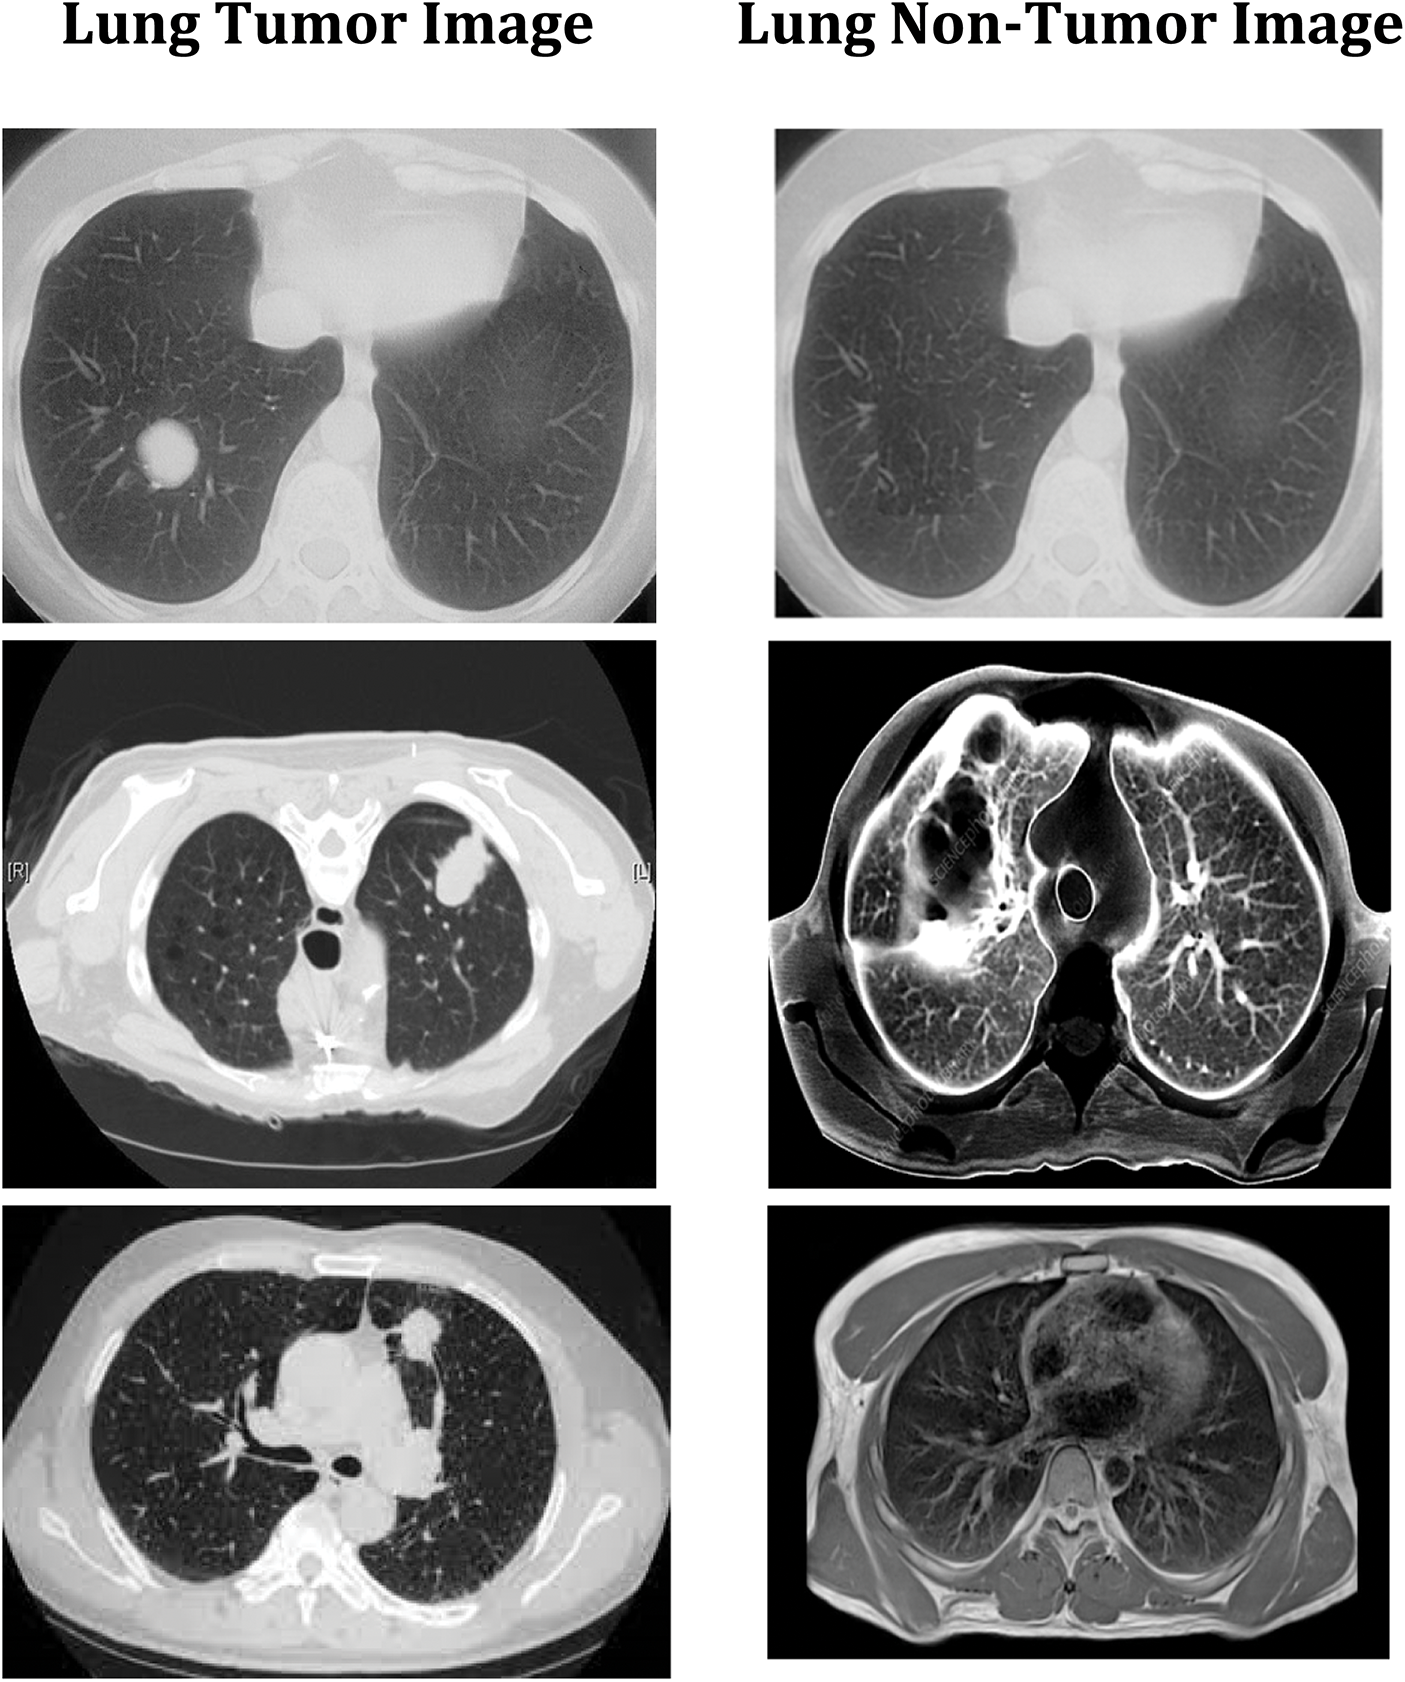

The convolution neural network is used in this study to accomplish effective automated lung cancer identification [33–35]. The Python programming language is used for simulation. After computing the precision, it is compared to all the other cutting-edge methods currently used. This method classifies lung cancers using the SVM technique. Utilizing the features extracted through the SVM, classification accuracy is computed based on the components extracted. SVM-based cancer and non-tumor identification process are time-consuming and imprecise. Hence, an alternative DWAE-DNN-based classification is proposed that does not need any distinct phases for feature extraction. Fig. 9 depicts the variety of cancer and non-neoplastic lung image. As a direct consequence, both the complexity and the amount of time spent computing are reduced while the accuracy increases. Fig. 10 presents the accuracy of lung cancer categorization output. The conclusion of the classification is either cancer lung or non-tumor lung, which is determined by the value of the probability score. The probability score associated with a standard lung image is the lowest possible score. Compared to normal lungs, cancer lung has the highest probability score value compared to normal lung.

Figure 9: DWAE-DNN classified observations